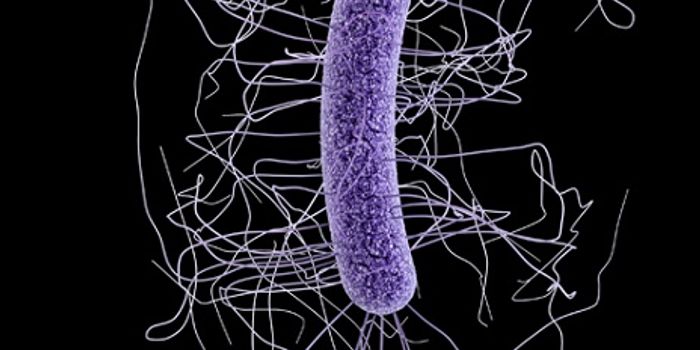

FEB 27, 2015Health & MedicineClostridium difficile (C. difficile, or C. diff) caused almost half a million infections among patients in the United St ...

FEB 27, 2015Health & MedicineATLANTA -- A nasty intestinal bug sickens nearly twice as many Americans each year as was previously thought, according ...

SEP 25, 2015MicrobiologyClostridium difficile is a Gram positive, rod-shaped bacterium commonly found in the soil. However, a small number ...